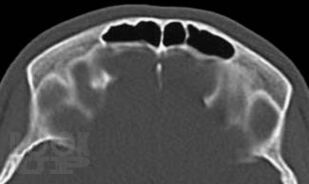

Рентгенографическая и компьютерно-томографическая диагностика острых и хронических синуситов

Монография посвящена применению классической рентгенографии и рентгеновской компьютерной томографии для диагностики острых и хронических воспалительных заболеваний околоносовых пазух. Результаты обоих исследований сопоставлены между собой по разработанной авторами методике, предложены адаптированные к практической работе подходы к обоснованному выбору указанных методов рентгенодиагностики синуситов. Книга хорошо иллюстрирована, содержит примеры описания рентгенограмм и компьютерных томограмм околоносовых пазух.

Книга рассчитана на врачей-рентгенологов, в том числе работающих на рентгеновских компьютерных томографах, врачей-оториноларингологов, интернов и ординаторов кафедр лучевой диагностики.